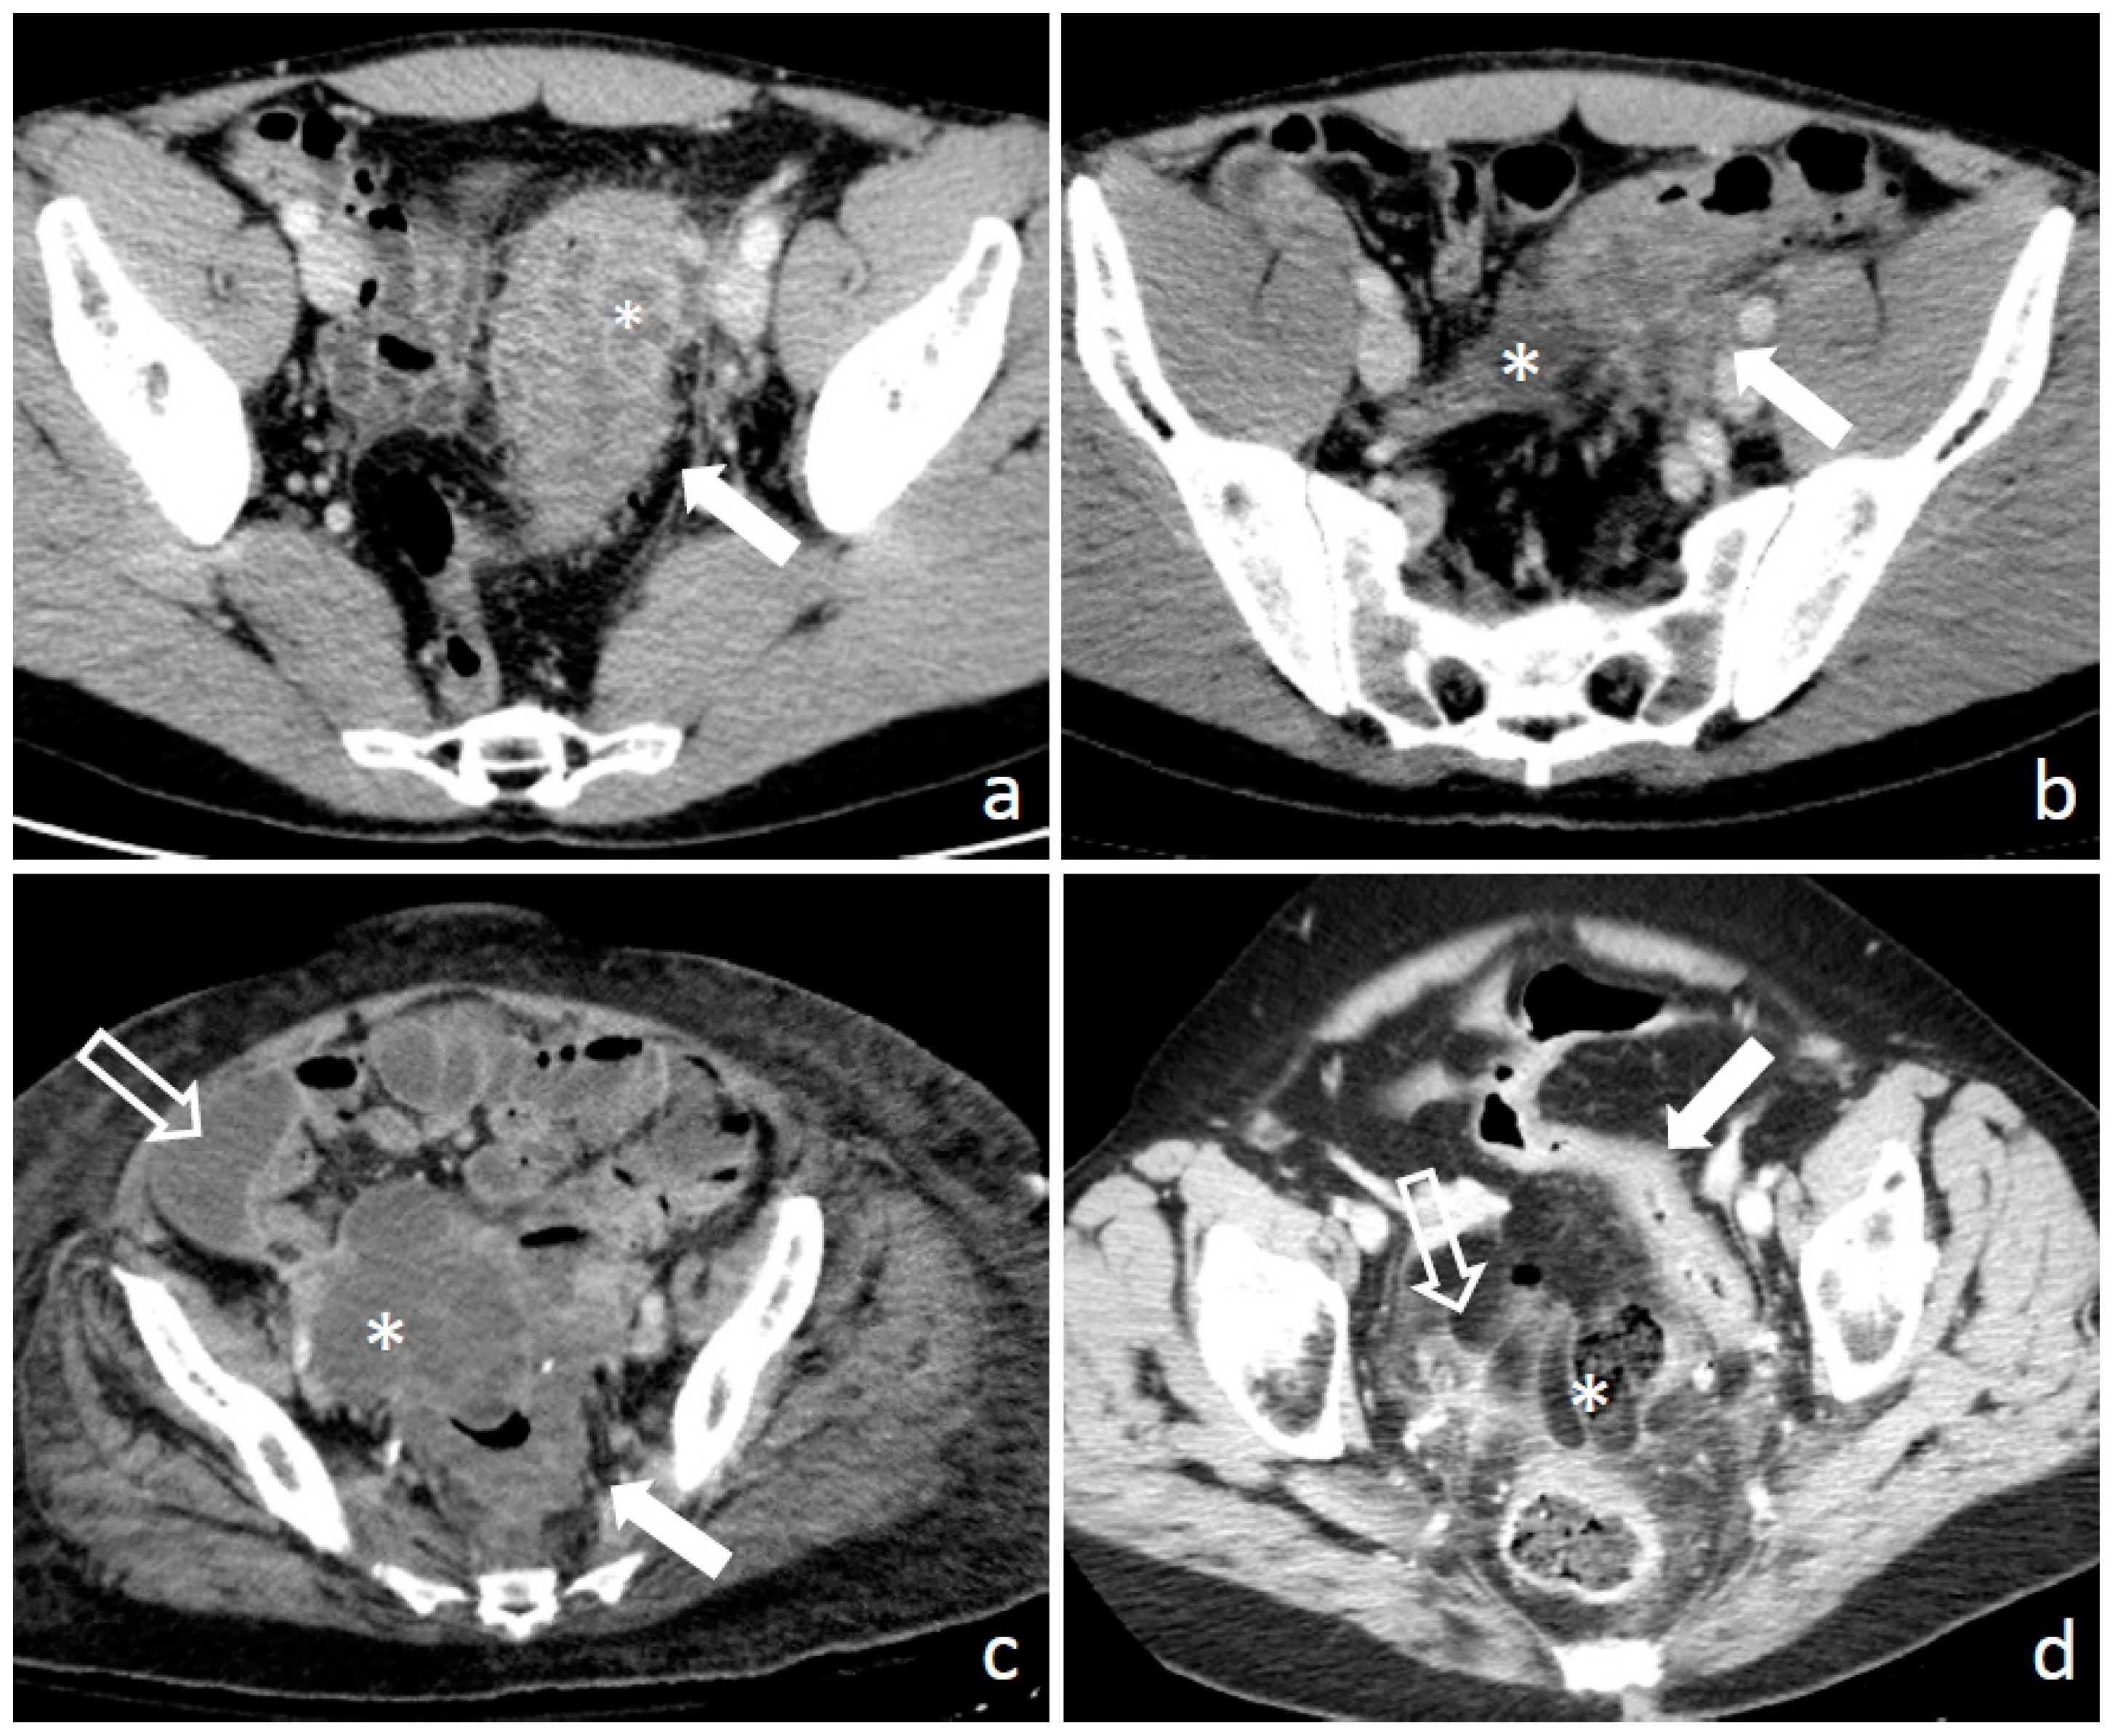

1.3. Diagnosis: Clinical Findings, Laboratory, Imaging, and Endoscopy